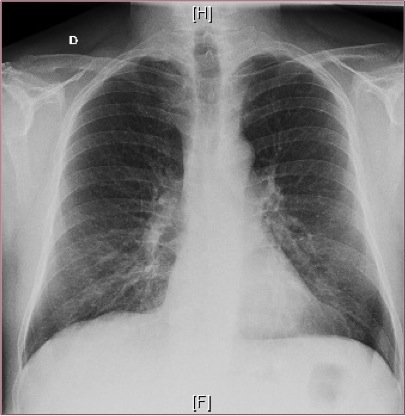

Urea 20, Cr 0,83, Na 136, K 4,1. - Estas son las

radiografías del paciente:

¿Que orientación diagnóstica te parecería más adecuada?